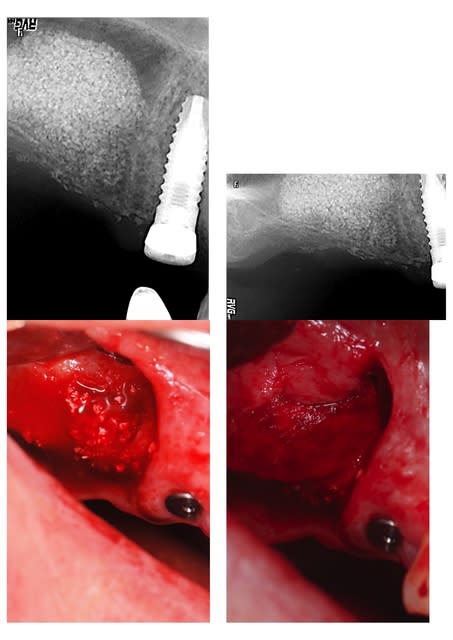

légende page 1: 1/implant 14 (posé en EII) 2 mois après extraction du bridge 14-17; 2/ zone de 17; 3/ lambeau ; 4/ séparation du volet; 5/ décollement de la membrane sans faire de bulles; 6/ 1er controle de remplissage

légende page 2 : 7/ fin du remplissage en 15; 8/ fin du remplissage en 17; 9/ avant pose de la membrane; 10/ après pose de la membrane

ben......une p'tite erreur! je n'ai pas assez reculé le bord mésial de ma fenêtre et j'ai découpé un bout de la zone où mon implant en 15 devait passer; c'est quand j'ai retiré le volet que je m'en suis aperçu! on le voit sur la photo avec le volet retiré, au 1/3 mésial de la zone de découpe, et on le devine sur les radios en comparant avant et après avec le biomat'; pas de blocage à l'apex, stabilité incertaine au niveau de la crête, j'ai préféré ne pas prendre de risque....mais j'avais bien prévu de les poser dans la même séance; j'ai donc comblé le défaut que j'avais créé dans la crête avec le biomat' et j'ai mis ma membrane par dessus; considérant que je poserai le 15 par la suite, le choix de le faire pour le 16 s'imposait, surtout que le scanner montrait déjà au départ une épaisseur limite à son sujet, inférieure à 2 mm